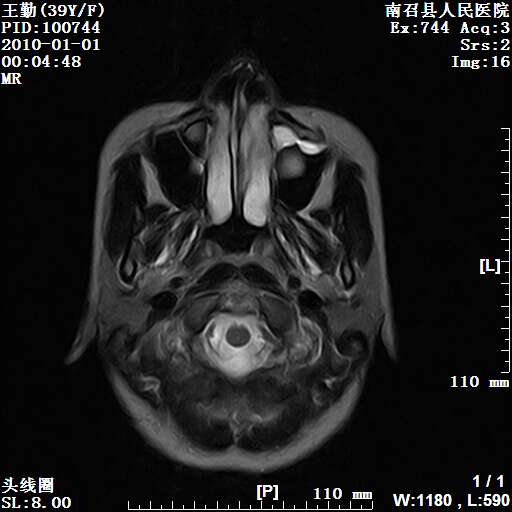

以下是引用随光逐影在2010-1-22 9:03:00的发言:[br]考虑左侧中颅窝(蝶骨翼区)脑膜瘤侵犯蝶骨翼并突入左侧眼眶。

以下是引用水过无痕在2010-1-22 14:55:00的发言:[br]一、定位:颅外占位;二、定性:恶性可能性大;三、组织来源:来源于左侧眼外直肌或其他部位;考虑为:横纹肌肉瘤>转移瘤>脑膜瘤.